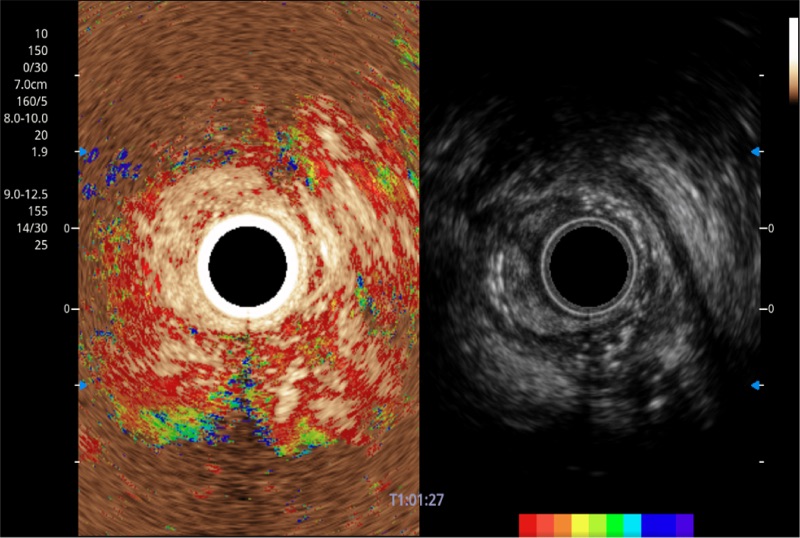

TIC时间强度分析曲线

具有四种造影成像效果

食管内间质瘤清晰显像

清晰显示胆总管及周围血管分布

肝左叶和肝静脉的横截面